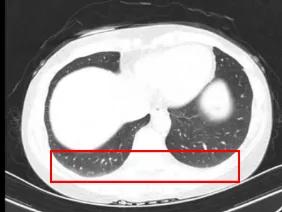

根据患者临床症状(手指雷诺现象、手指肿胀及皮肤增厚)(如图1-1)、胸部CT发现早期轻度肺纤维化(如图1-2)、SSc特异性抗体(抗着丝点抗体强阳性)(如图1-3)等情况,考虑可以明确诊断为“系统性硬化症”。